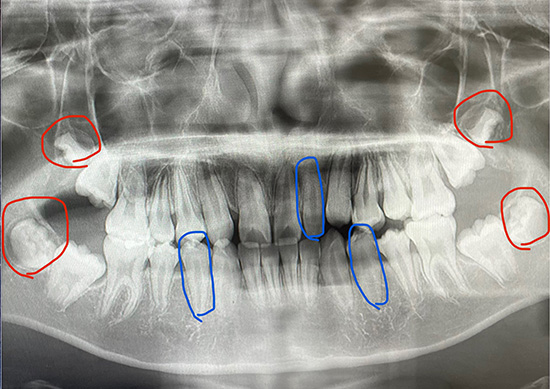

赤い丸がまだ生えていない親知らずの歯。青い丸が抜歯予定の歯。

今の歯の状態を石膏模型で確認しましたが、奥に行けば行くほどひとつひとつの歯が一回り大きいために顎に収まりきらず、12歳臼歯(じゅうにさいきゅうし)の生えてくる場所が少ないということでした。そして、レントゲンではさらに奥に親知らずの歯が12歳臼歯の歯に当たって邪魔をしているということでした。

矯正をしてもしなくても、12歳臼歯に当たっている下の歯の親知らずの2本の歯は抜かないといけないそうです。幸い、まだ歯の根元が神経に当たっていないのでそこまで痛くはないだろうという予想でした。矯正の話はいつもそうですが、ほんとため息がでます。

そして、今回の歯列矯正では上顎の矮小歯を1本抜歯、上下の歯のかみ合わせの数を合わせるため、2本の第4臼歯も抜歯するプランを説明されました。健康な下の歯を2本も抜くなんて嫌だなと伝えると、その場合、上の矮小歯をそのまま置いておいて下の第4臼歯を1本だけ抜歯するプランもあると追加説明を受けました。

上下ともに少し斜めに出ている歯。顎に収まりきっていないよう。